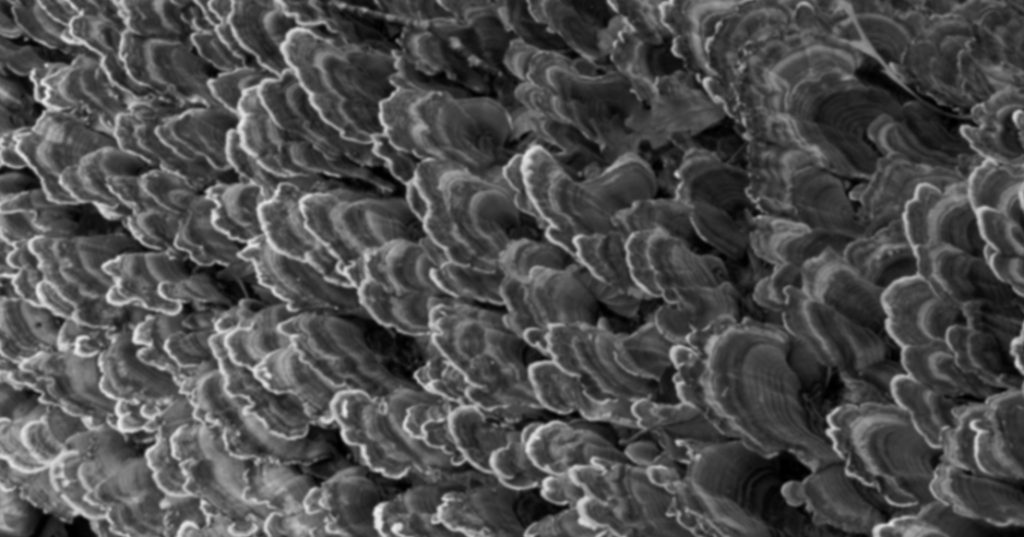

To solve some of the challenges in dentin bonding cited by Tay and Pashley, I air-abrade the completed preparation with 50-micron aluminum oxide. Other authors have shown increased retention just from roughening the dentin with a diamond if you don’t have access to air abrasion.